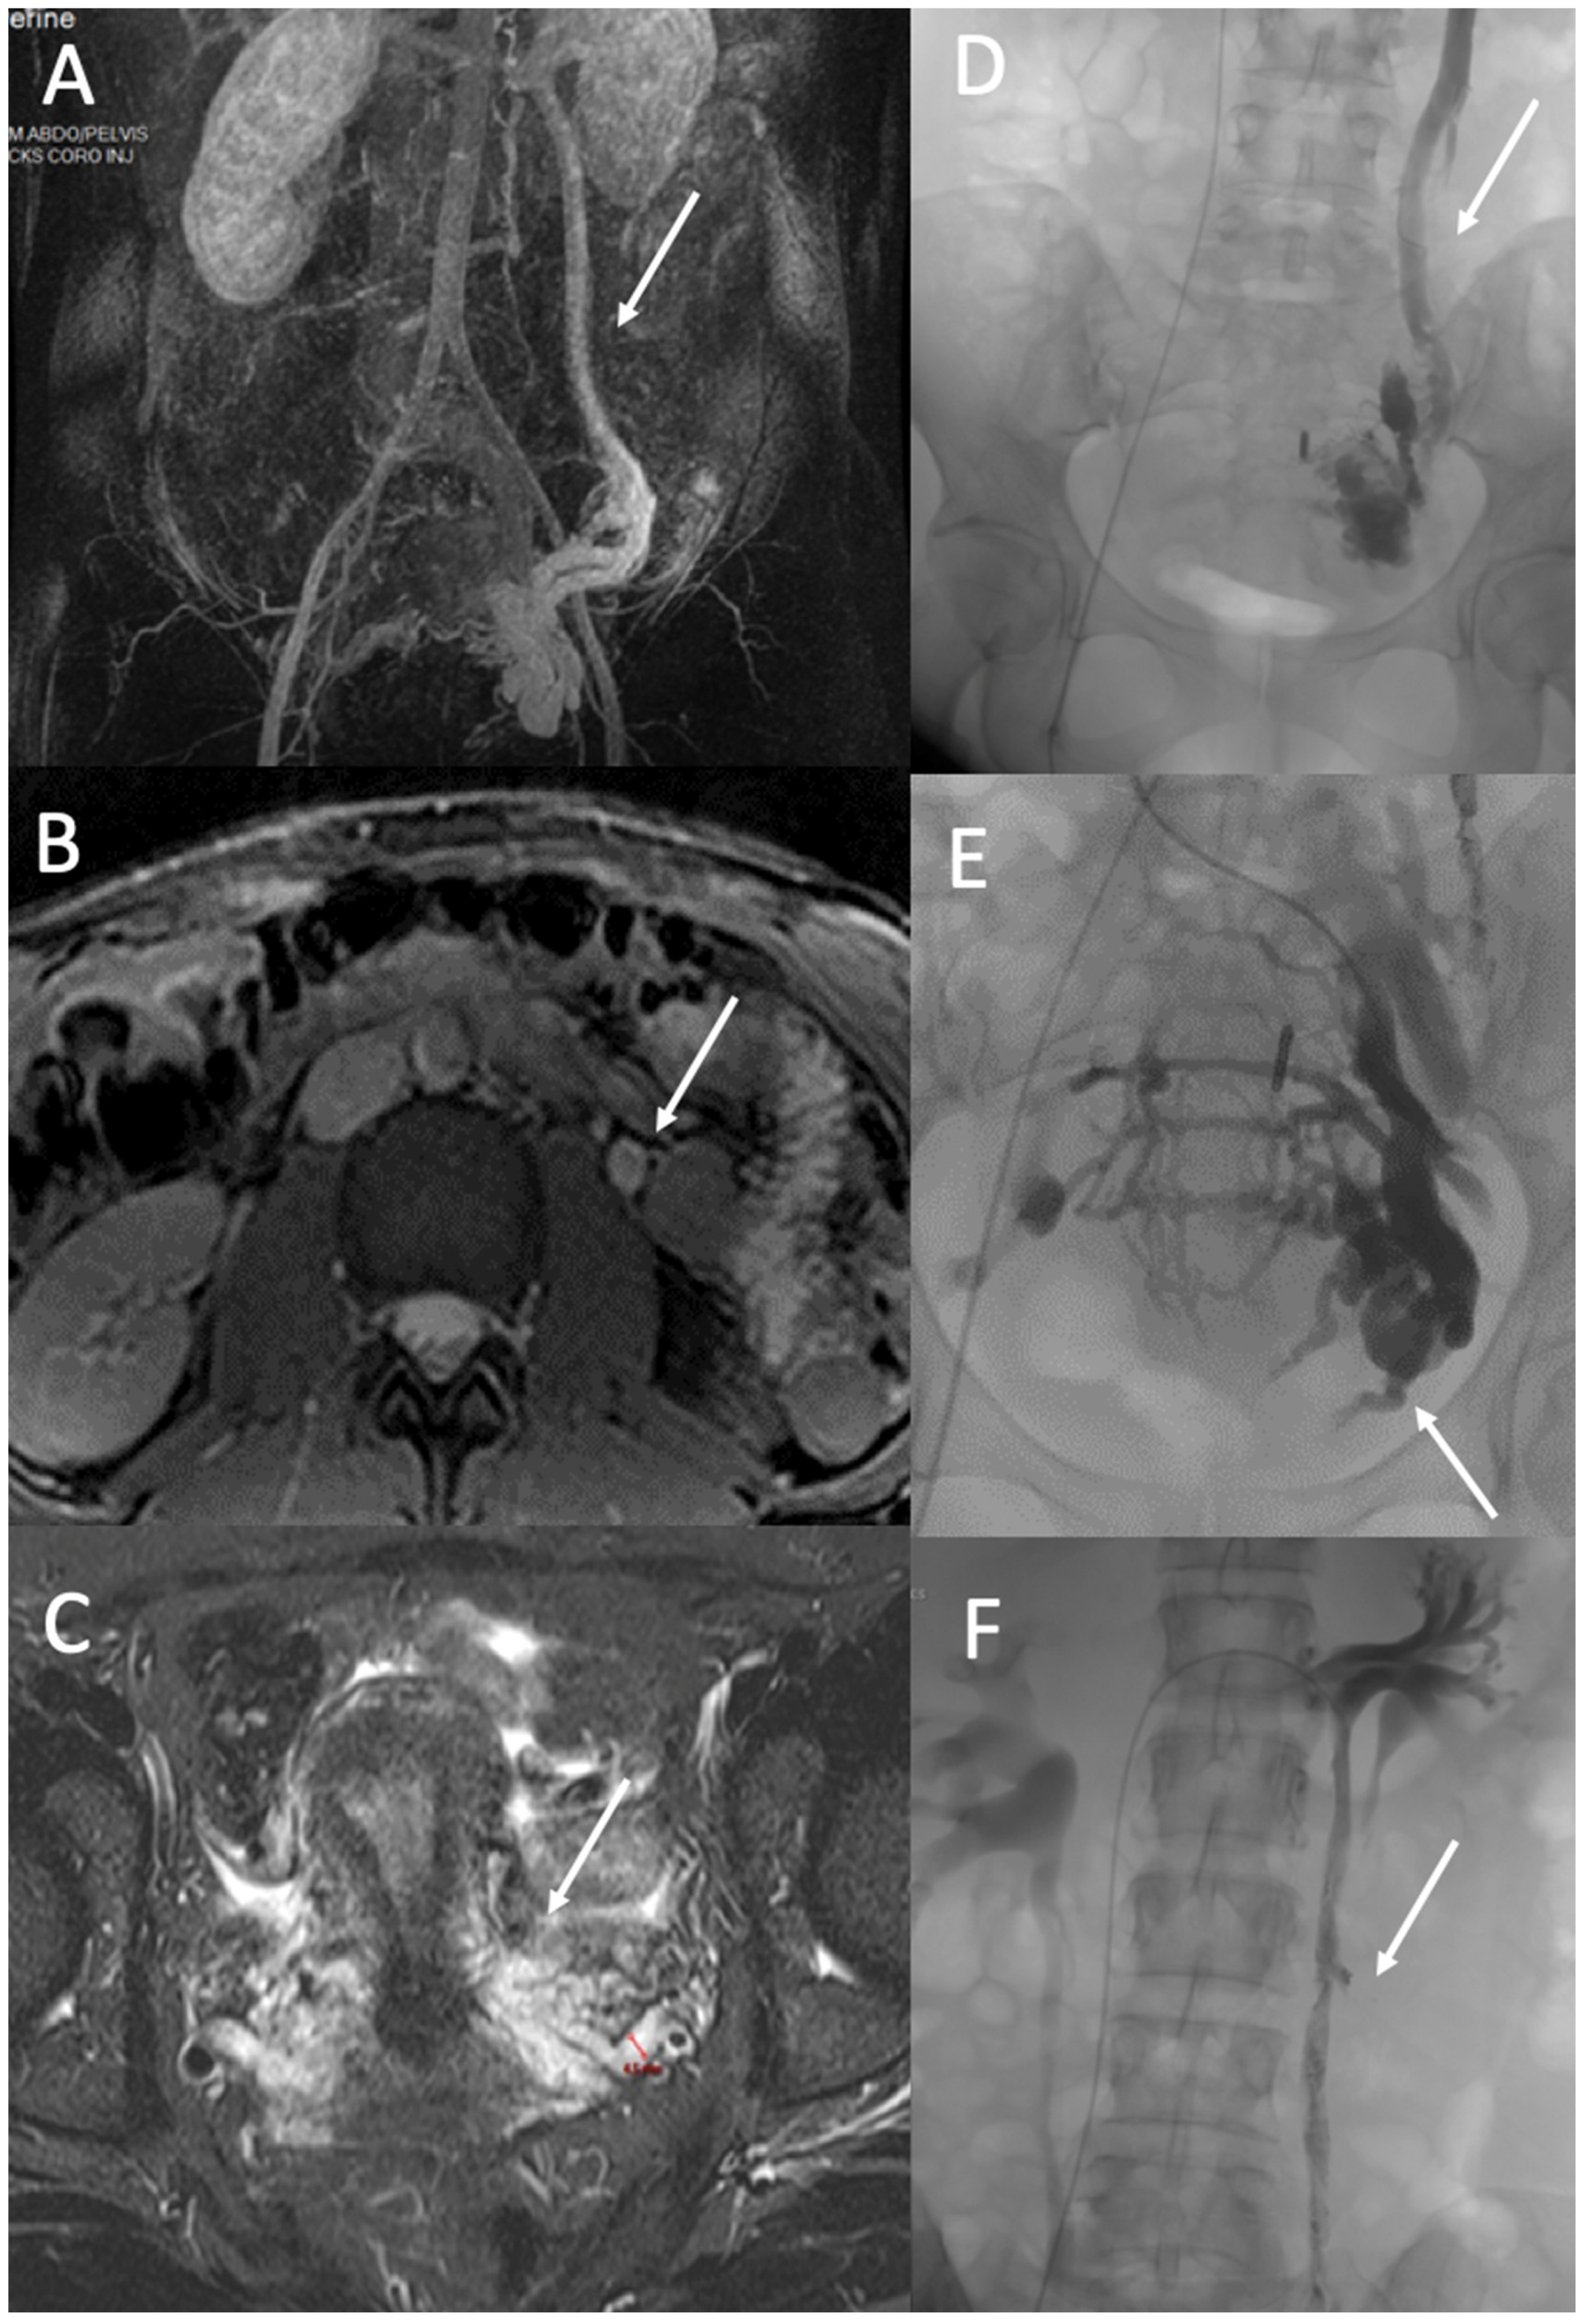

4.2. Ovarian and Iliac Venous Insufficiency

4.3. Vulvar and Lower Limb Varices of Pelvic Origin